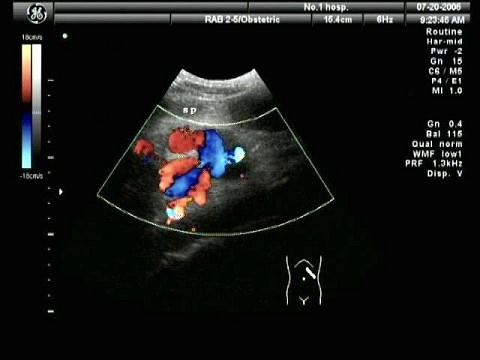

问题 彩色多谱勒血流显像的彩色图通常采用什么彩色表示血流方向?(?)

选项 A.红色表示血流朝向探头,蓝色表示血流背离探头 B.红色表示血流背离探头,蓝色表示血流朝向探头 C.蓝色表示血流朝向探头,白色表示血流背离探头 D.红色表示血流背离探头,白色表示血流朝向探头 E.可随意设定

答案 A